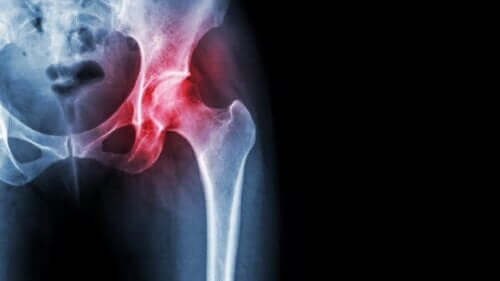

Knochennekrose des Oberschenkelknochens

Knochennekrose wird wie jede Nekrose durch eine mangelnde Blutversorgung des Gewebes verursacht. Es handelt sich um ein ernstes Problem, das schwerwiegende Folgen haben kann.